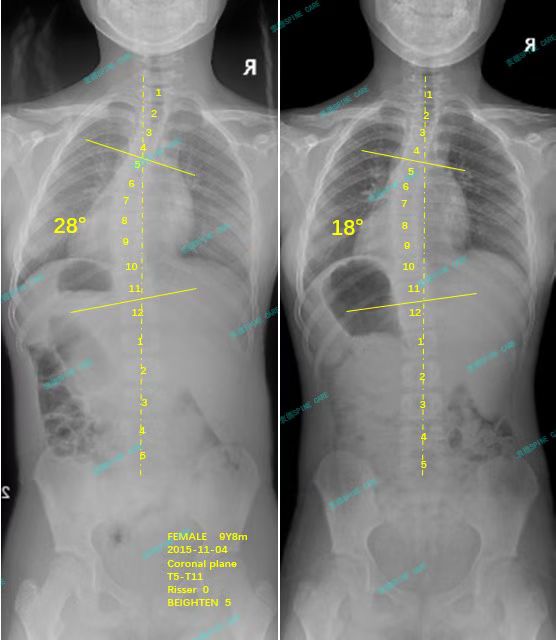

衷德脊柱,我们只关注侧弯保守治疗~

Zhongde Spine, bending no breaking ~